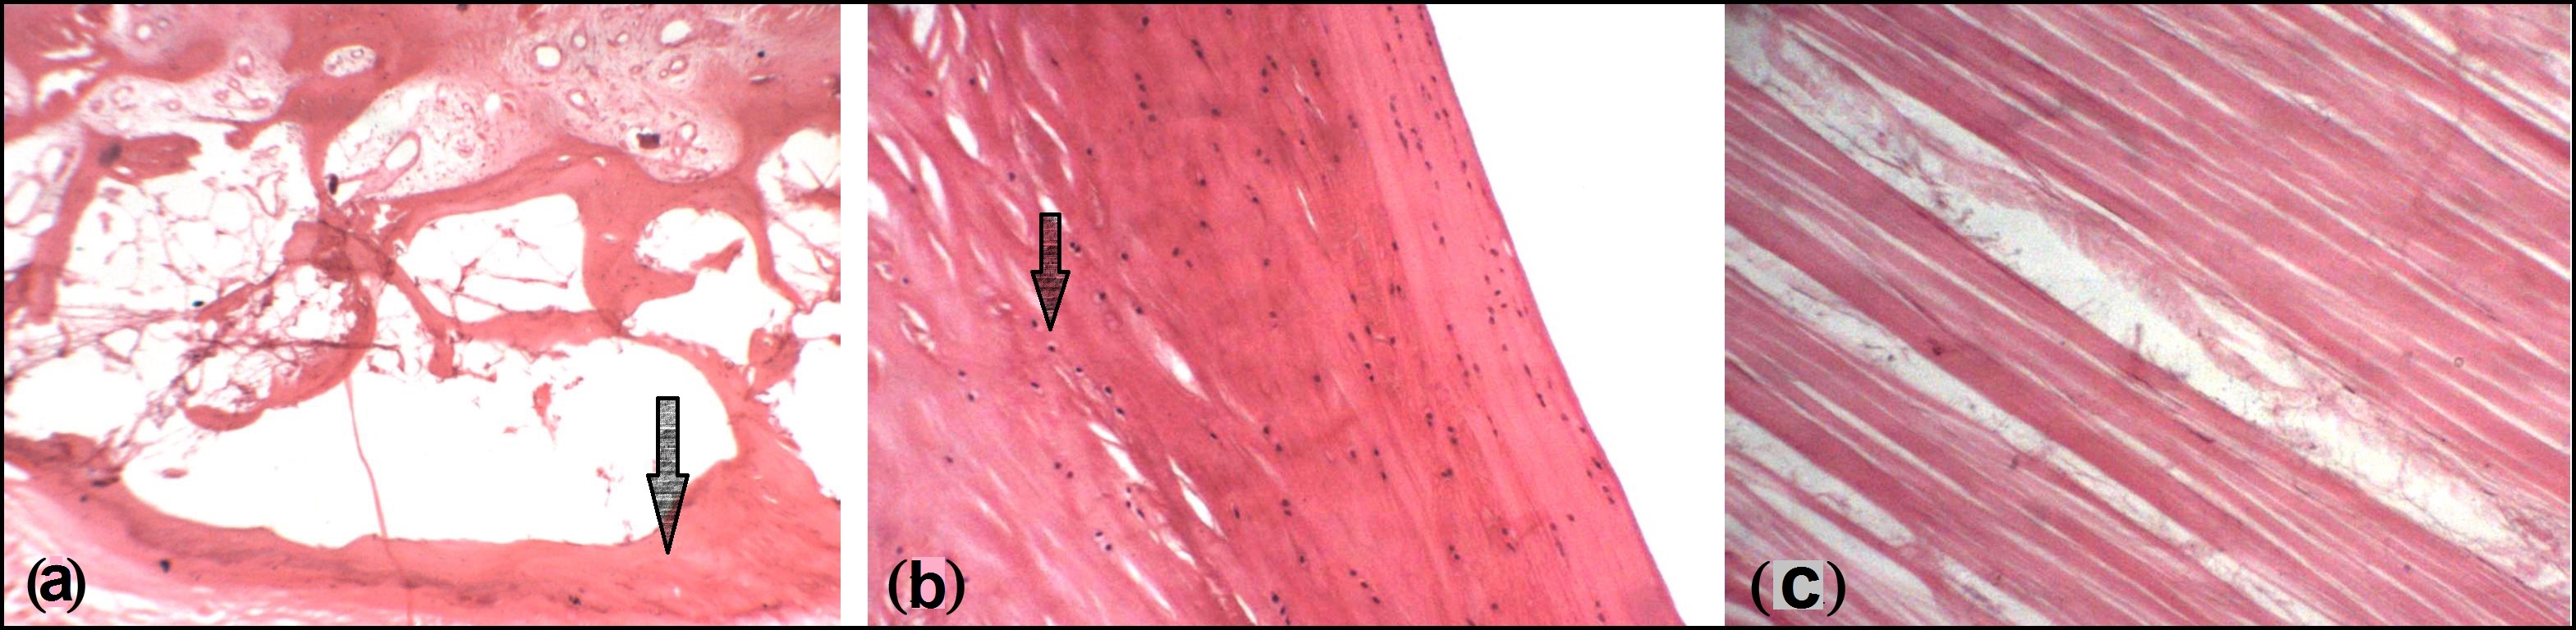

Histologically, OP were either cancellous bone [Table/Fig-6a], fibrocartilage [Table/Fig-6b] or only thickened collagen fibres [Table/Fig-6c].

6]: Photomicrographs of OP showing (a) Cancellous bone (b) Fibrocartilage (c) Collagen fibres [H&E (10X)]

Muehleman et al., stated that 30% tendons displayed an OP both radiologically and histologically [8]. We've found that the OP was either cancellous bone or fibrocartilage or mere thickening of collagen fibres. Where OP was present as a hypertrophy of collagen bundles, the deep surface was covered by fibrocartilage or hyaline cartilage. In the present study, the average length of OP was 13.14 mm, average breadth of OP was 8.96 mm & average thickness of OP was 4.11 mm; but as the literature reviewed does not show similar parameters being studied by other workers; hence, no comparison can be drawn.